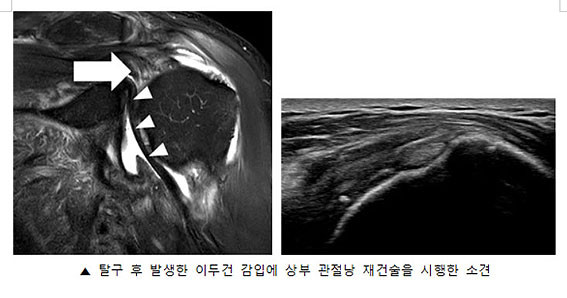

À̹ø ¿¬±¸¿¡¼ À¯À缺 ±³¼ö´Â ¾î±ú Å»±¸¿Í µ¿¹ÝµÈ ±¤¹üÀ§ ȸÀü±Ù°³ ¼Õ»ó ȯÀÚ¿¡°Ô À̵ΰÇÀ» ÀÌ¿ëÇÑ »óºÎ°üÀý³¶ Àç°Ç¼úÀ» ½ÃÇàÇÏ¿© ȯÀÚÀÇ Áõ»óÀÌ È£ÀüµÇ´Â °á°ú°¡ ³ªÅ¸³µÀ½À» È®ÀÎÇß´Ù.

| | ¡è¡è ¡ãÀ̵ΰÇÀ» ÀÌ¿ëÇÑ »óºÎ °üÀý³¶ Àç°Ç¼ú <»çÁøÁ¦°ø=Ãæ¹«º´¿ø> | ¨Ï ¿Â¾ç½Å¹® | |

| | ¡è¡è ¡ã Å»±¸ ÈÄ ¹ß»ýÇÑ ÀÌµÎ°Ç °¨ÀÔ¿¡ »óºÎ °üÀý³¶ Àç°Ç¼úÀ» ½ÃÇàÇÑ ¼Ò°ß <»çÁøÁ¦°ø=Ãæ¹«º´¿ø> | ¨Ï ¿Â¾ç½Å¹® | |